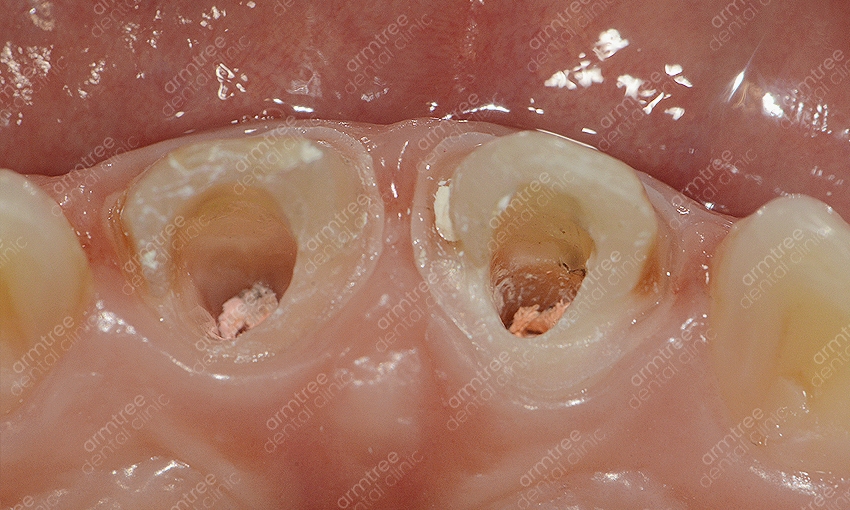

실활치란 용어는 외상이나 충치 등으로 인하여 치아 속 치수가 죽는 증상을 의미해요. 그로 인해 혈액과 신경 활동이 원활하게 이루어지지 않아 치아가 약해지고 어둡게 변하기도 하는 것이에요. 이러한 치아 내부의 출혈 색소나 염증 부산물을 제거하는 신경치료를 선 진행한 후 치아 내부에 미백제를 넣어 다시 치아색을 밝게 한 후 레진으로 막는 치료법이에요. 일반적인 생활치미백에 비해 진행과정이 까다로운 편이기 때문에 관련하여 장비를 갖추고 있고 해당 경험이 풍부한 곳에서 치료를 받는 것이 좋았어요. 신논현역치과 아름드리치과에 사용되는 약재에 대해 신체에 해로울까 걱정하시는 분들도 계시는데요. 사용되는 약재는 치아 속에 과산화수소수 계열의 약재를 넣어놓고 환자가 생활하시는 동안에 미백이 진행되게 하는 것이라 영어로는 Walking blwaching라고도 불리는데요. 실제로 진행 시 치아 하부 구조 사이에 수복재료를 쌓고 진행하는 것이라 전문 의료진과 함께 한다면 크게 위험하지 않은 시술이라고 할 수 있었어요. 하지만 이 역시 정확하게 수복재료를 적용하지 않고 무분별한 진행을 한다면 치아 외 흡수가 발생할 수 있으므로 받드시 경험이 많은 의료진의 시술이 필요한 과정이었어요.

실활치미백은 치아가 전체적으로 변색되어 하는 일반적인 치아미백과는 다른 것이 특정치아 특히 앞니만 변색되거나 1-2개의 치아의 색이 변한 경우 진행하는 경우가 많은데요. 치아 1-2개의 색만 검게 변한다면 전체적으로 누렇거나 하얗지 못하게 되었을 때 보다 더 어색하거나 튀어서 도드라지게 보일 수 있기에 적절한 치료를 통해 주변 치아의 색과 유사하도록 해주는 것이 효과적이에요. 또 일반적인 치아미백이라면 미백제의 농도 조절이나 미백 광선의 조사방법이 중요한데 실활치미백은 먼저 신경치료가 선행되어야 하기에 보다 정교한 시술이 필요해요. 신경조직은 여러 갈래로 나뉘어져 섬세한 치료를 요하는 시술이기 때문인데요. 신논현역치과 아름드리치과에서는 3D 첨단 장비를 구비하고 있어 세세한 부분까지 신경치료를 진행할 수 있을 뿐 아니라 항시 임상경험이 풍부한 의료진이 대기하고 있어 정확하고 안전한 시술을 기대할 수 있었어요. 또 신논현역치과에서는 환자 개인마다 다른 환자의 구강환경에 맞춰 1:1 맞춤 플랜을 세워 치료를 진행하고 있었어요. 아름드리치과는 앞니 단일 치아의 변색일 때에는 외상으로 인한 치아 신경의 염증, 치아의 신경인 치수 잔사 등 미세한 염증이 존재하는 경우, 기존 신경치료 후 레진 수복 후 레진 수복재료사이의 미세누출로 염증이 생긴 경우 등 다양한 경우의 원인이 있을 수 있어요. 그렇기에 보다 정확한 진단 검사와 그에 따른 치료계획을 수립하는 것이 중요한 과정이라 볼 수 있었어요. 미백치료의 경우 집에서 셀프로도 많이들 진행하시지만 미백 후에 효과가 별로 없다거나 1-2의 치아만 유독 변색이 심하다면 집에서 직접 하는 방식으로는 치료가 불가능하기에 꼭 신논현역치과 아름드리치과를 내원하시길 권해드리겠어요.